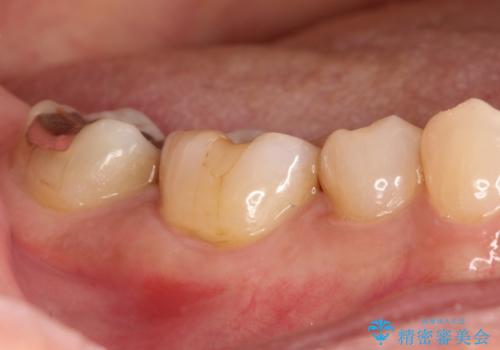

奥歯が痛い。精密根管治療〜オールセラミッククラウン

根管治療〜オールセラミッククラウン(エクセレント)の治療を行なっております。

- 精密根管治療(イニシャルケース,大臼歯):122,000円、ファイバーコア:22,000円、仮歯:11,000円、オールセラミッククラウン(エクセレント):200,000円費用は治療当時の料金となります

根管治療後の最終補綴物は予後に大きく関わります。